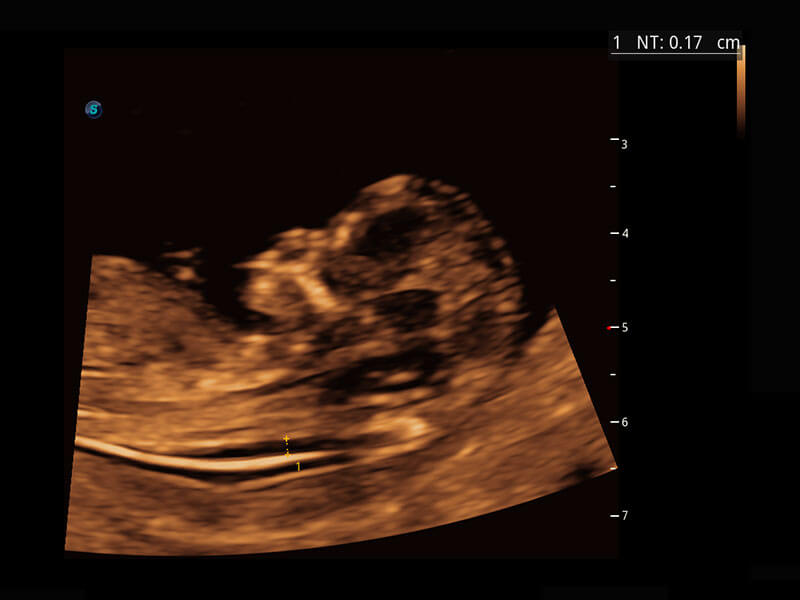

P60搭载一系列胎儿心脏成像技术,实现精细的胎儿心脏评估。

四腔切面

胎心容积成像